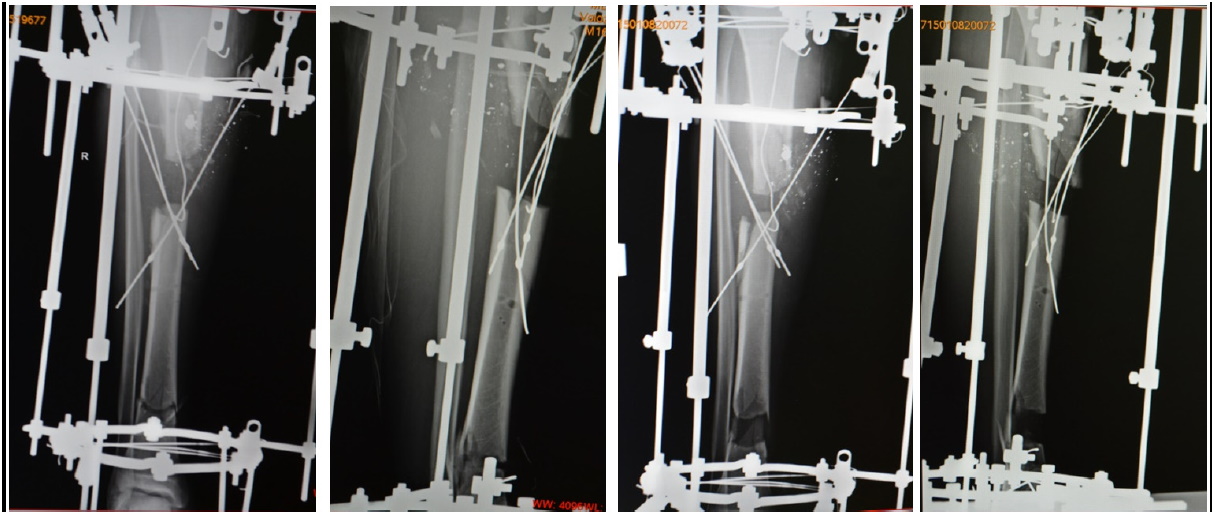

Больной В., 16 лет. Переведен из лечебного учреждения по месту жительства через 10 дней после травмы. Получил огнестрельное ранение из ружья с расстояния около 1,5 м. В момент травмы сидел, высоко закинув правую согнутую в коленном суставе ногу на левый коленный сустав. Это привело к ранению правой голени в верхней трети с продолжающимся ударом пули о внутреннюю часть левого бедра в области надмыщелка, далее потерявшая кинетическую энергию пуля ушла кверху по внутренней части бедренной кости вверх почти до ягодичной складки. Выполнена первичная обработка раны с первичной фиксацией перелома в карбоновом стержневом аппарате. При ревизии раны выявлено повреждение передней большеберцовой артерии (рис. 1). В стационаре по месту жительства проведена экономная первичная хирургическая обработка раны. Визуально при поступлении определяемые размеры повреждения кожи были внешне небольшими. Однако через 12 дней после перевода в краевую детскую больницу размеры дефекта с некрозом кожи и подлежащих тканей достигли 4 ´ 5 см. После снятия швов с раны выявлены множественные свободные отломки без адаптации, канал дистального отломка загрязнен некротическими тканями. Между отломками – участок дефекта. Выявлены очаги некроза мягких тканей, сгустки крови, участки размозжения тканей, детрит как следствие дистрофических процессов от ранения. При ревизии оказалось, что передняя большеберцовая артерия повреждена на протяжении с образованием большого дефекта. Все свободные отломки, некротизированные участки тканей и гнойное отделяемое удалены. Сформировался свищевой ход, уходящий в икроножную мышцу. Жизнеспособность ушибленных участков кости с явлениями некроза, отсутствием кровоснабжения расценена как сомнительная для хорошей адаптации и сращения, велика угроза дальнейшего развития остеомиелита.

Рис. 1. Рентгенограммы больного В., 16 лет, при поступлении. Оскольчатый перелом большеберцовой кости в верхней трети, загрязнение огнестрельной раны. Отломки зафиксированы в стержневом карбоновом аппарате

Решено создать костный дефект в пределах жизнеспособных тканей с целью последующего замещения. С помощью осциллирующей пилы отломки адаптированы по форме за счет косопоперечного опила. Образовался острый дефект размерами около 5 см длиной. Часть пристеночного отломка большеберцовой кости на надкостнице оставлена с латеральной стороны, через проксимальный отдел дистального отломка проведены четыре спицы-вожжи, одна из них – спица Киршнера, загнутая крючком с фиксацией за край компактной кости, остальные с напаем. Для лучшей адаптации и возможного ограниченного применения следующего этапа перемонтажа спицы-вожжи проведены одновременно через дистальный отломок, дефект и проксимальный отломок для обеспечения восстановления соосности в процессе дистракции кости в дефект. Проведена кортикотомия дистального отломка в метадиафизарной дистальной области на удлинение. Для проведения кортикотомии использован следующий прием: временно установлено кольцо с поперечно проведенной спицей в нижней трети большеберцовой кости, после состоявшейся кортикотомии спица и кольцо удалены, проксимальный и дистальный сегменты окончательно соединены тремя телескопическими стержнями. Концы выведенных над кожей спиц-вожжей закреплены в тракционных устройствах. Стопа находилась в эквинусном положении без возможности активной тыльной флексии, поэтому дополнительно фиксирована в аппарате. Трубчатый дренаж – в основном по заднему краю раны и части свищевого хода. Вторым доступом длиной 4 см в положении на животе под контролем электронно-оптического преобразователя в верхней трети по задней поверхности левого бедра удален свинцовый пулевой фрагмент в виде скрученной пластины неправильной конической формы длиной около 1 см, максимальный размер поперечника 0,7 см. Начата дистракция с целью замещения дефекта большеберцовой кости (рис. 2).

Рис. 2. Рентгенограммы после первого этапа замещения дефекта кости и в процессе дальнейшей дистрации отломка большеберцовой кости с помощью спиц-вожжей